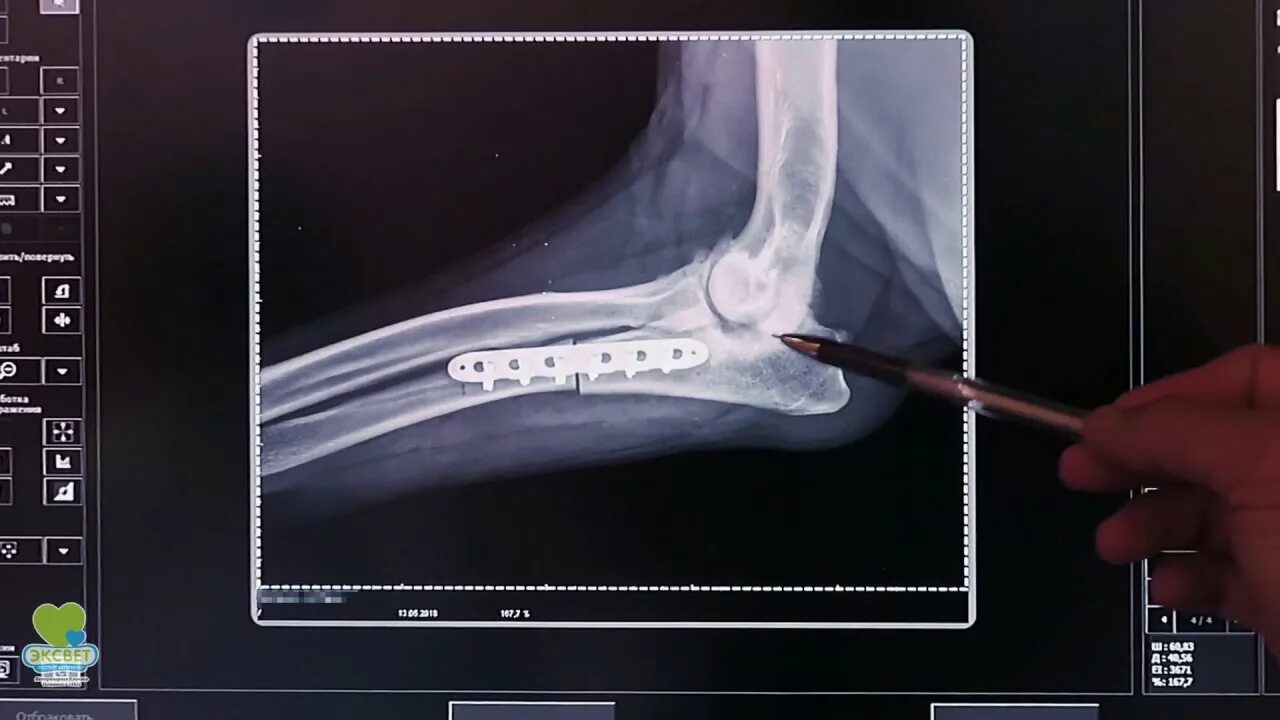

Операция суставов собак